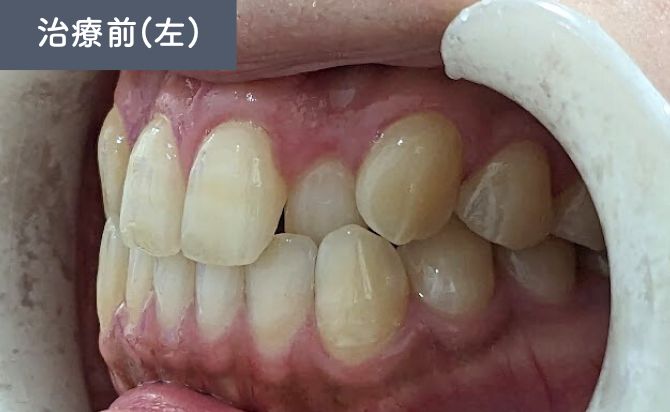

歯並びの変化(左)

上顎1番の前方位が確認され、口元の突出感に影響していました。また、上顎2番の舌側傾斜があり、歯列全体の並びにも不均衡がみられました。

さらに、下顎歯列弓が方形型であることから、上下のアーチ形態のバランスが整っておらず、前歯部の噛み合わせにも改善の余地があると判断しました。

治療終了時には、患者様が気にされていた上顎1番の突出が軽減され、前歯の位置が適正化しました。上顎2番の舌側傾斜も改善され、左右のバランスが整った歯列アーチが得られています。

右側3番の切端咬合も改善し、犬歯誘導が適切に働く咬合状態となりました。上下のアーチ形態のバランスも改善し、見た目だけでなく、機能的にも安定した咬合が確立されています。